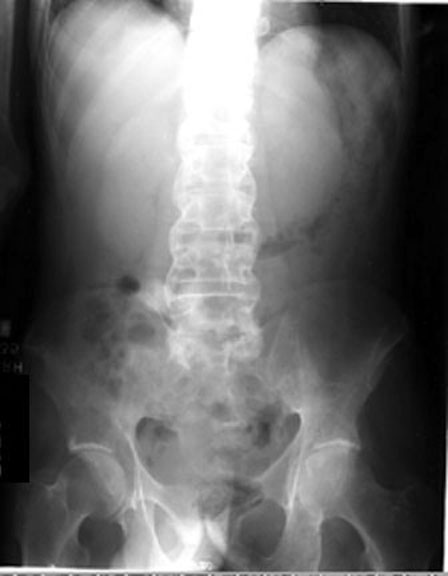

Figure-3 “Bamboo Spine” appearance of Ankylosing spondylitis. III. Discussion: AFI in ankylosed spine or a C-Spine injury is considered as a gold standard.However its successful execution requires a significant background experience and high clinical expertise. ... Retrieve Content

Ankylosing spondylitis (spondylitis ankylopoietica, Bechterew’s syndrome, spondylitis ankylosans) · Inflammatory diseases G 03 1 referred to as a “bamboo spine” in the advanced stage. • Pelvis and lumbar spine showing slight degenerative changes ... Fetch Doc

SAJR September 2012 Vol. 16 No. 3 111 PICTORIAL ESSAY Ankylosing spondylitis (AS) is one of the sero-negative spondylo-arthropathies.1 This group of arthritides is characterised by specific ... Access Content

PowerPoint Presentation

Bamboo spine and bilateral sacroiliitis. X-ray . showing syndesmophytes . Even in patients with longer-standing disease, syndesmophytes are present in ... Get Document